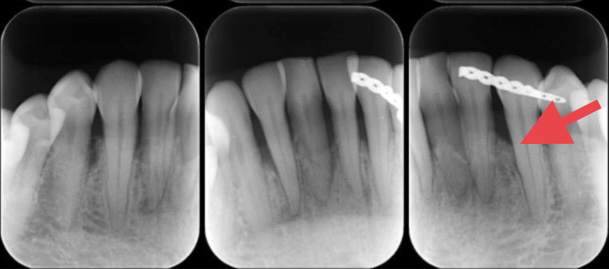

それでは詳細のレントゲンで骨の状態を確認していきましょう。赤の矢印が骨の位置を示しています。

歯周組織再生療法後(外科処置の6ヶ月後)

白く写っているのはワイヤーです。

歯周組織再生療法後に噛み合わせによる負担がかからない様に固定をしています。

この方は全ての処置が完了した後も上手に歯磨きをされ、決められた期間でのメインテナンスにもきちんと来られているので、現在も良い状態をキープされております。

この方は、部分的(垂直的)な骨の吸収だったので、今回の治療が適応でしたが、全体的に骨の吸収がある場合は抜歯になる事もございます。